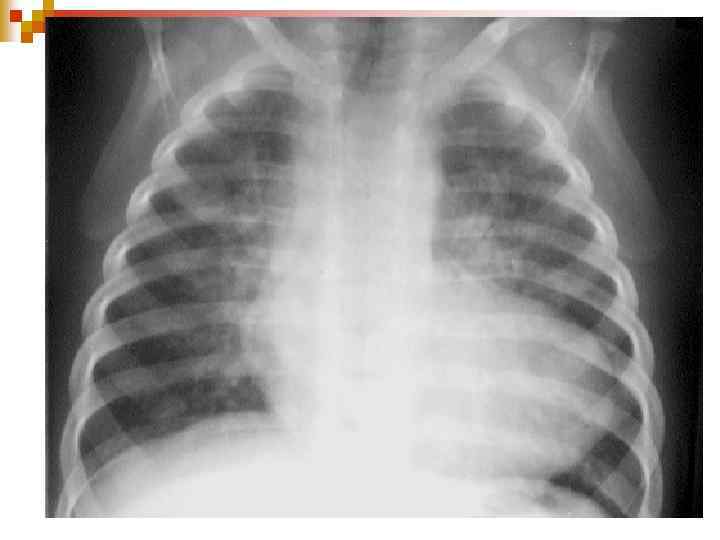

Клініка ЗЦ нападу ЕКГ: гіпертрофія ПШ та гіпоксія міокарду; n ЕХО-КГ – визначає величину зміщення аорти, ДМШП, ступінь легеневого стенозу, гіпертрофії ПШ; n Рентгенологічно – серцева тінь має форму дерев’яного чобітка. n